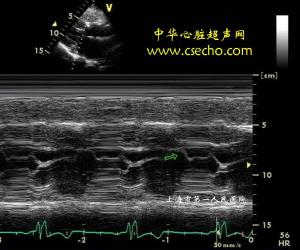

3、超聲心動圖:是一項重要的非侵入性診斷方法。主要表現有①室間隔異常增厚,舒張期末的室間隔厚度>15mm。②室間隔運動幅度明顯降低,一般≤5mm。③室間隔厚度/左室後壁厚度比值可達1.5-2.5:1,一般認為比值>1.5:1已有診斷意義。④左心室收縮末內徑比正常人小。⑤收縮起始時間室隔與二尖瓣前葉的距離常明顯縮小。⑥二尖瓣收縮期前向運動,向室間隔靠近,在第二心音之前終止。⑦主動脈收縮中期關閉。以上7項應綜合分析,方能得出正確結論,應注意高血壓病,甲狀腺機能低下,均可引起類似表現。

肥厚型心肌病超聲心電圖2、主動脈瓣狹窄症狀和雜音性質相似,但雜音部位較高,並常有主動脈瓣區收縮期噴射音,第二音減弱,還可能有舒張早期雜音。X線示升主動脈擴張。生理動作或藥物作用對雜音影響不大。左心導管檢查顯示收縮期壓力差存在於主動脈瓣前後。超聲心動圖可以明確病變部位。